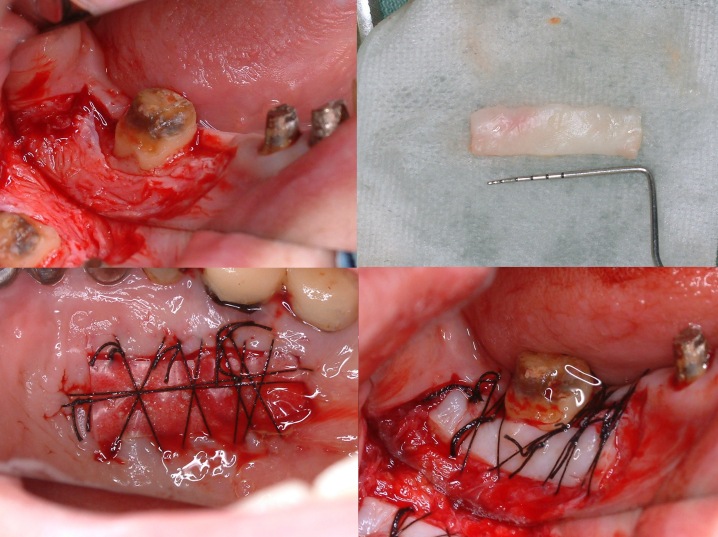

術直後のレントゲン写真です。

術後8か月 術後8か月 |

術後15か月CT所見 術後15か月CT所見 |

術前 術前 |

術後15か月CT所見 術後15か月CT所見 |

術前で破壊されていた部分に骨の再生が認められるため、黒かった部分が白くなっていることがわかります。

再生療法時 骨が失われている部位 骨が失われている部位 |

再生療法後 再生した部位 再生した部位 |

| 失われていた骨の再生が認められます。 | |

CT所見で見られたのと同様に再生療法を行った部位にみられた骨欠損は骨様組織にて満たされていることがわかります。